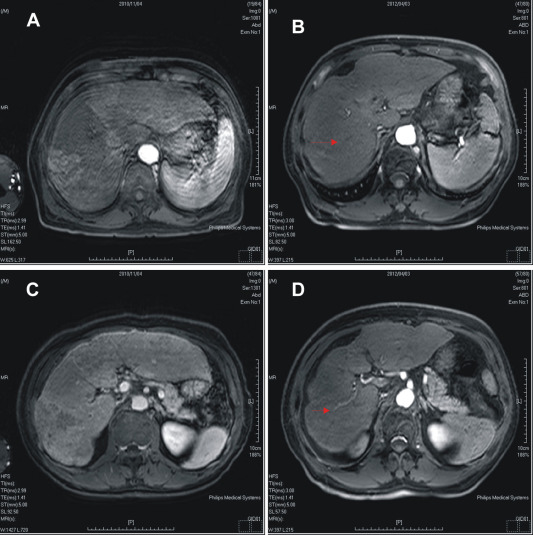

Effect of treatment with sorafenib and radiotherapy evaluated by abdominal ...

Figure 3.

Effect of treatment with sorafenib and radiotherapy evaluated by abdominal magnetic resonance imaging. (A), (B) Pretreatment and post-treatment in arterial phase. Part (B) also shows decreased tumor size in arterial phase after treatment (arrow); (C), (D) pretreatment and post-treatment in delayed phase. Part (D) also shows decreased tumor thrombus in the portal vein after treatment (arrowhead).

The patients symptoms improved gradually with no abdominal pain and his appetite improved. The follow-up examination 6 months later indicated an early response, with a dramatic reduction in the size of the liver masses (8 cm to 3 cm) and a decrease in the α-fetoprotein level. He experienced manageable side-effects of mild diarrhea, itching of the skin with red papules over his scalp, Grade 2–3 hand and foot skin reactions, lesser control of hypertension, and some hair loss. On completion of 16 months of treatment he had ongoing marked clinical, radiological, and biochemical responses (Figure 2 , Figure 3  ;  Figure 4 ).